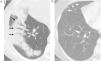

Although there is no strict definition of the pattern of organising pneumonia as in other idiopathic interstitial pneumonias, the characteristic pattern of this disease could be considered to include patchy consolidations and ground-glass opacities in the peribronchial and subpleural areas of both lungs. Moreover, studies of the course of the disease show that these lesions respond to treatment with corticoids, migrate with or without treatment, and tend to recur when treatment is decreased or withdrawn.

Other manifestations of organising pneumonia include nodules of different sizes and shapes, solitary masses, nodules with the reverse halo sign, a perilobular pattern, and parenchymal bands.